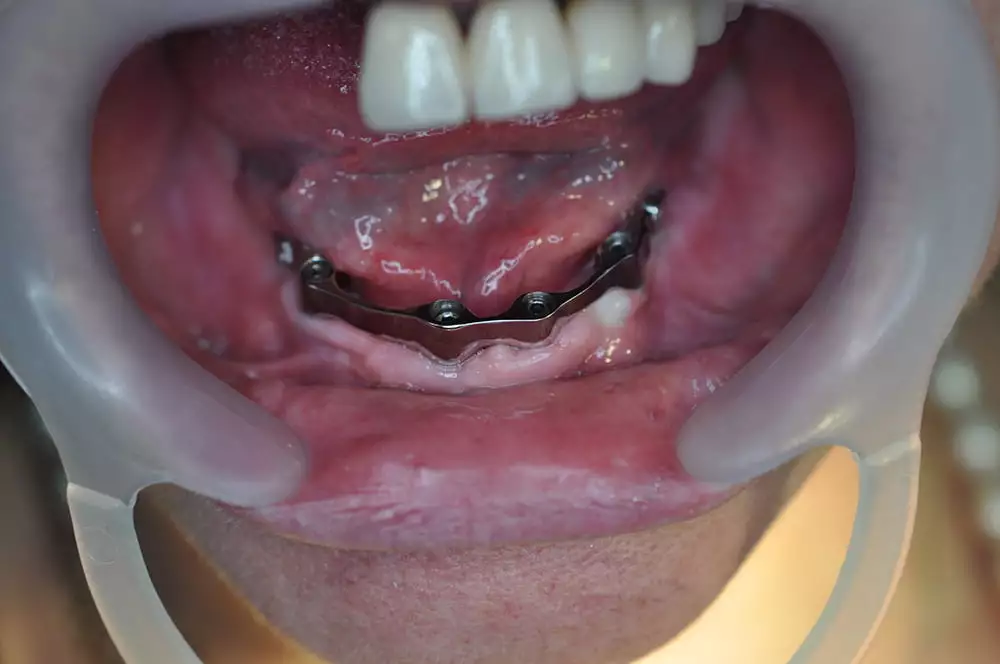

Было произведено удаление пораженных шатающихся зубов верхней челюсти с подготовкой к этапу имплантации и установление коронок, а также произведена имплантация 4 имплантатами Osstem нижний челюсти, выполнено тотальное протезирование полным съемным балочным протезом с опорой на 4 имплантанта Osstem (Ю.Корея), с фиксацией МК-1 замками.